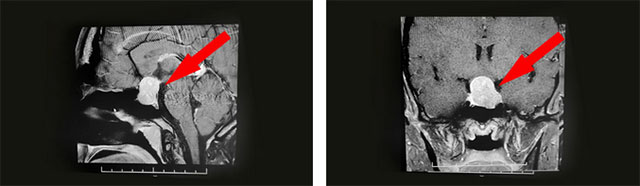

經(jīng)過(guò)醫(yī)院仔細(xì)檢查發(fā)現(xiàn):鞍區(qū)MRI平掃+增強(qiáng)顯示:蝶鞍擴(kuò)大,鞍底骨質(zhì)下陷;鞍內(nèi)垂體可見(jiàn)類(lèi)橢圓形異常信號(hào),大小約2.5*1.6cm,垂體柄未見(jiàn)明顯顯示;鞍上結(jié)構(gòu)尚清,視交叉上抬;病灶與雙側(cè)海綿竇分界清晰;所示蝶竇局部黏膜增厚。

結(jié)合病史、影像等,神經(jīng)外科6B病區(qū)潘仁龍主任、李士其教授、吳治群博士會(huì)診后考慮為混合性泌乳-生長(zhǎng)激素垂體大腺瘤,正是垂體瘤導(dǎo)致莉莉月經(jīng)異常并停經(jīng),以及面容改變、肢端粗大等。手術(shù)指征明確,應(yīng)盡快手術(shù)治療。

▲ 影像檢查顯示:垂體大腺瘤,超蝶鞍生長(zhǎng)